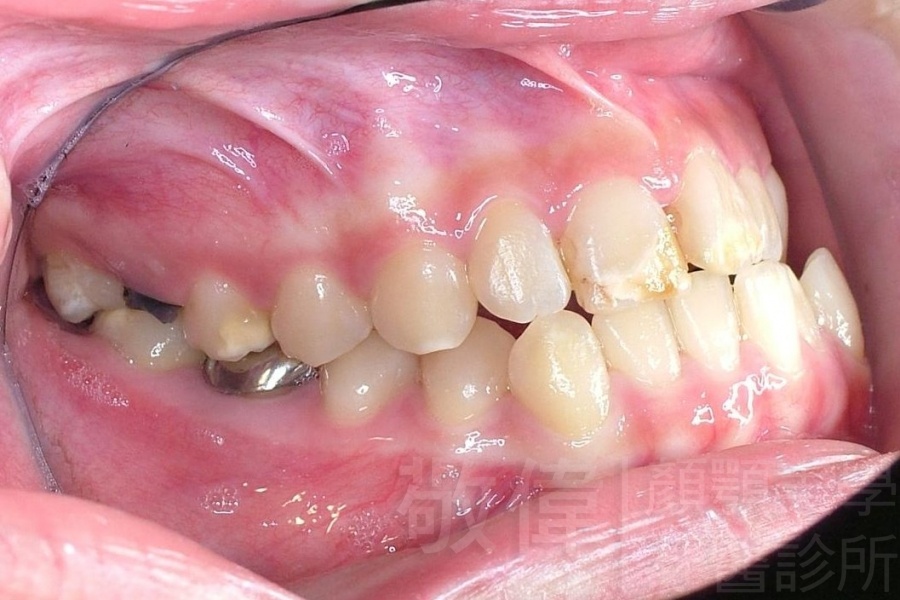

變臉矯正,原來戽斗妹跟大歪臉變成自信正妹

經由本院3D數影X光影像儀分析、與3D齒顎顏矯正技術,再配合口腔顎面正顎專科醫師施以正顎手術治療,雙方共同合作,使患者臉部外觀有很好的改善,大歪變小歪,產生了天南地北的大改變,她的人生也整個變得不一樣。

因為矯正與正顎手術的配合,使「戽斗妹」變成了「陽光正妹」,完全的改變了她的人生,在面對各種場合、與人交際都散發出自信微笑。所以,奉勸家長,如果小朋友有臉顎畸型的問題,應該考慮配合做這種簡單、安全、有效的正顎手術。

「3D齒顎顏矯正」,不止矯正您的牙齒,也會改變您的人生。「治療前」和「治療後」出社會的人生際遇一定會截然不同。